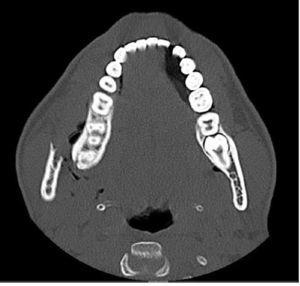

Se sol·licità radiografia simple (fig. 1), que mostrà fractura completa de la branca mandibular dreta i fractura lineal parasimfisària esquerra. Com que no es disposava d’ortopantomografia d’urgència se sol·licità tomografia computeritzada mandibular, que evidencià fractura desplaçada de l’angle mandibular dret amb emfisema subcutani (fig. 2) i fractura parasimfisària esquerra no desplaçada.

Figura 2. Fractura desplaçada de l’angle mandibular dret, amb emfisema subcutani, d’un jugador d’hoquei herba de 17 anys amb contusió facial directa.

Per al diagnòstic de les fractures mandibulars, la radiografia panoràmica o ortopantomografia proporciona una primera visió general molt acceptable, però en molts serveis d’urgències aquesta prova no està disponible. En aquesta situació la radiologia simple amb projecció AP (fig. 1) de Towne i obliqua lateral dreta i esquerra generalment permet visualitzar la fractura, però en cas de radiografia aparentment normal i sospita diagnòstica alta, cal sollicitar una tomografia computeritzada mandibular (fig. 2). La tomografia computeritzada és l’estudi òptim per visualitzar la mandíbula en tots els plans i, sobretot, els còndils, que freqüentment s’han desplaçat per la tracció de la musculatura masticatòria i es troben fora del pla, per la qual cosa a vegades les fractures a aquest nivell passen desapercebudes amb proves radiològiques convencionals.